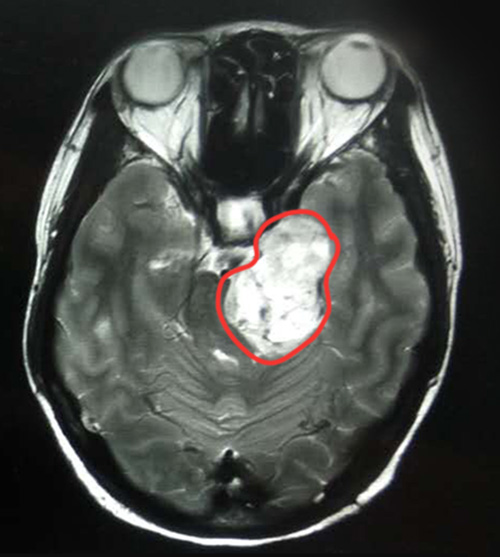

陳女士的MRI影像診斷報告單很快出來了,結(jié)果讓她大吃一驚。MRI影像顯示,患者左側(cè)橋小腦角區(qū)見團(tuán)塊狀異常信號病灶,邊界清晰,大小約4.8*3.3厘米,腫瘤呈啞鈴狀生長,左側(cè)三叉神經(jīng)顯示不清,臨近腦干受壓,第四腦室受壓變形,是一枚體積不小的三叉神經(jīng)鞘瘤。

▲MRI影像顯示,左側(cè)橋小腦角區(qū)有一4.8*3.3厘米的腫瘤